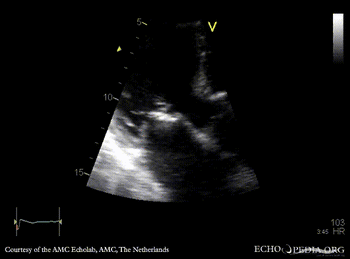

Endocarditis of mitral valve

A3CH: vegetations on AMVL A2CH